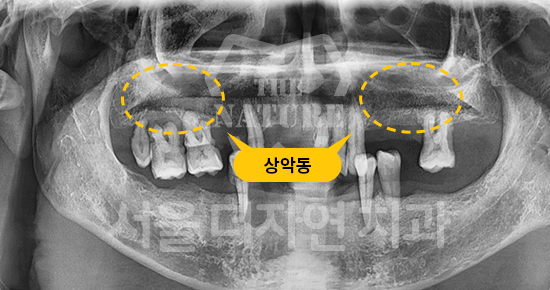

#상악 골이식

-

BEFORE: 2021.11.02

AFTER: 2022.01.19